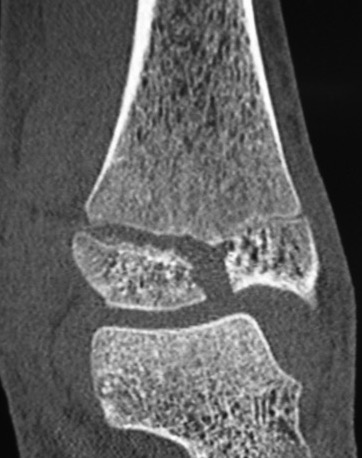

Triplanar Fracture

Definition

Fracture in coronal, sagittal and transverse planes

- crosses epiphysis

- passes through growth plate

- extends into metaphysis

Xray

AP xray: Salter-Harris type III / Tillaux

Lateral xray: Salter-Harris Type II

CT

Coronal images: Salter-Harris type III

Sagittal images: Salter-Harris type II

Axial images: 3 point star